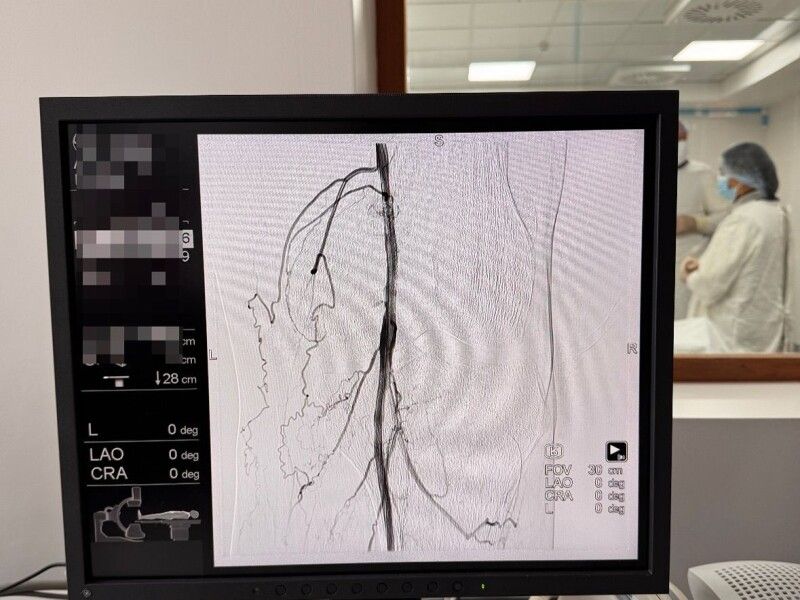

Клінічний стан: критична ішемія, кровотік припинився нижче підколінної артерії. Стан настільки важкий, що зазвичай такі випадки закінчуються ампутацією

Після обстеження судинний хірург КНП «Нововолинська ЦМЛ» прийняв рішення боротися за кінцівку. Було проведено балонну ангіопластику та стентування підколінної артерії справа. На операційному столі сталося диво – кінцівка «ожила», відновився кровотік.